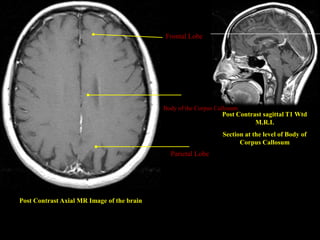

Body of the Corpus Callosum

Post Contrast sagittal T1 Wtd

M.R.I.

Section at the level of Body of

Corpus Callosum

Parietal Lobe

Post Contrast Axial MR Image of the brain